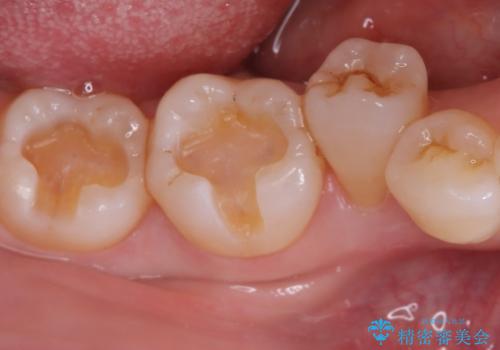

メタルインレーを除去した際、古い裏層材やカリエスは除去し新たにCR裏層しています。

セラミックインレーセット時はラバーダム防湿を行っています。